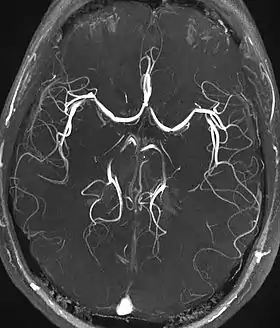

Magnetic resonance angiography (MRA) generates pictures of the arteries to evaluate them for stenosis (abnormal narrowing) or aneurysms (vessel wall dilatations, at risk of rupture). MRA is often used to evaluate the arteries of the neck and brain, the thoracic and abdominal aorta, the renal arteries, and the legs (called a "run-off"). A variety of techniques can be used to generate the pictures, such as administration of a paramagnetic contrast agent (gadolinium) or using a technique known as "flow-related enhancement" (e.g., 2D and 3D time-of-flight sequences), where most of the signal on an image is due to blood that recently moved into that plane (see also FLASH MRI).[39]

Techniques involving phase accumulation (known as phase contrast angiography) can also be used to generate flow velocity maps easily and accurately. Magnetic resonance venography (MRV) is a similar procedure that is used to image veins. In this method, the tissue is now excited inferiorly, while the signal is gathered in the plane immediately superior to the excitation plane—thus imaging the venous blood that recently moved from the excited plane.[40]